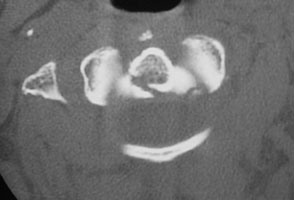

- Click on the image for a larger versionBAxial CT. This shows a fracture of the base of the odontoid (Type II).